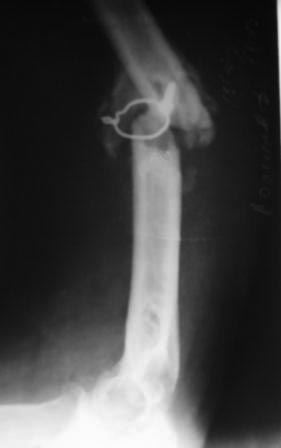

Пациент 1942г.р. 4 –месяца назад оперирован в экстренном порядке в другом областном неотложном центре, 20 дней назад гипс снят и направлен к нам. Пациент активный, оптимист, никогда ничем не болел. Локально: тугой ложный сустав с варусной деформацией, клиника полного повреждения лучевого нерва (со слов до операции также рука висела), контрактура локтевого сустава , разгибательная контрактура л/з сустава и пальцев, воспалительных изменений нет. От предложенного БИОС по финансовым соображениям отказался. Предварительный план лечения: удаление металлоконструкций, ревизия лучевого нерва (возможно, пластика нерва), освежение концов до появления "росы", и адаптация концов возможно по типу "русского замка", фиксация либо аппаратом Илизарова, либо пластиной (у нас обычные пластины ЦИТО типа DCP), возможно укорочение на 2-3 см, но это для плеча большого значения не имеет, главная ранняя и усиленная разработка движений в суставах руки. Уважаемые коллеги, не осуждайте строго за банальность, я пишу про то, что имеем и сможем , и если можно прошу помочь советом, или примерами из практики. С уважением Абдурашид.

Уважаемые коллеги, прошу прощения за задержку ответа. Операцию проводили 27.11.13г по настоятельной просьбе докторов там, где был оперирован, поэтому пришлось долго ждать контроль.Р-грамму и самого больного, только сегодня приехали. Операция более 4 часов, во время операции установлено полное повреждение лучевого нерва, концы булавовидно утолщены, дефект 2,5-см, с трудом и очень долго пришлось мобилизовать, частично был замурован костной мозолью . Кость укорочена на 3 см, пластика типа русского замка, в это время часть дистального отломка откололась, поэтому пришлось фиксировать винтом, и еще косо спицей., и/м 4-мя спицами, шов нерва, под нервом слой мышца, АВФ из двух колец с компрессией. Р-снимки прилагаются.